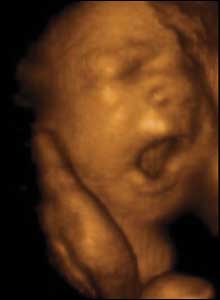

29 weeks gestation. 28cm from crown to rump.

10 of 10

Babies produce a motion approximating to yawning from as early as 12 weeks' pregnancy. Maybe this is nature's way of ensuring that as soon as she enters the world, she'll be able to take her first breath.